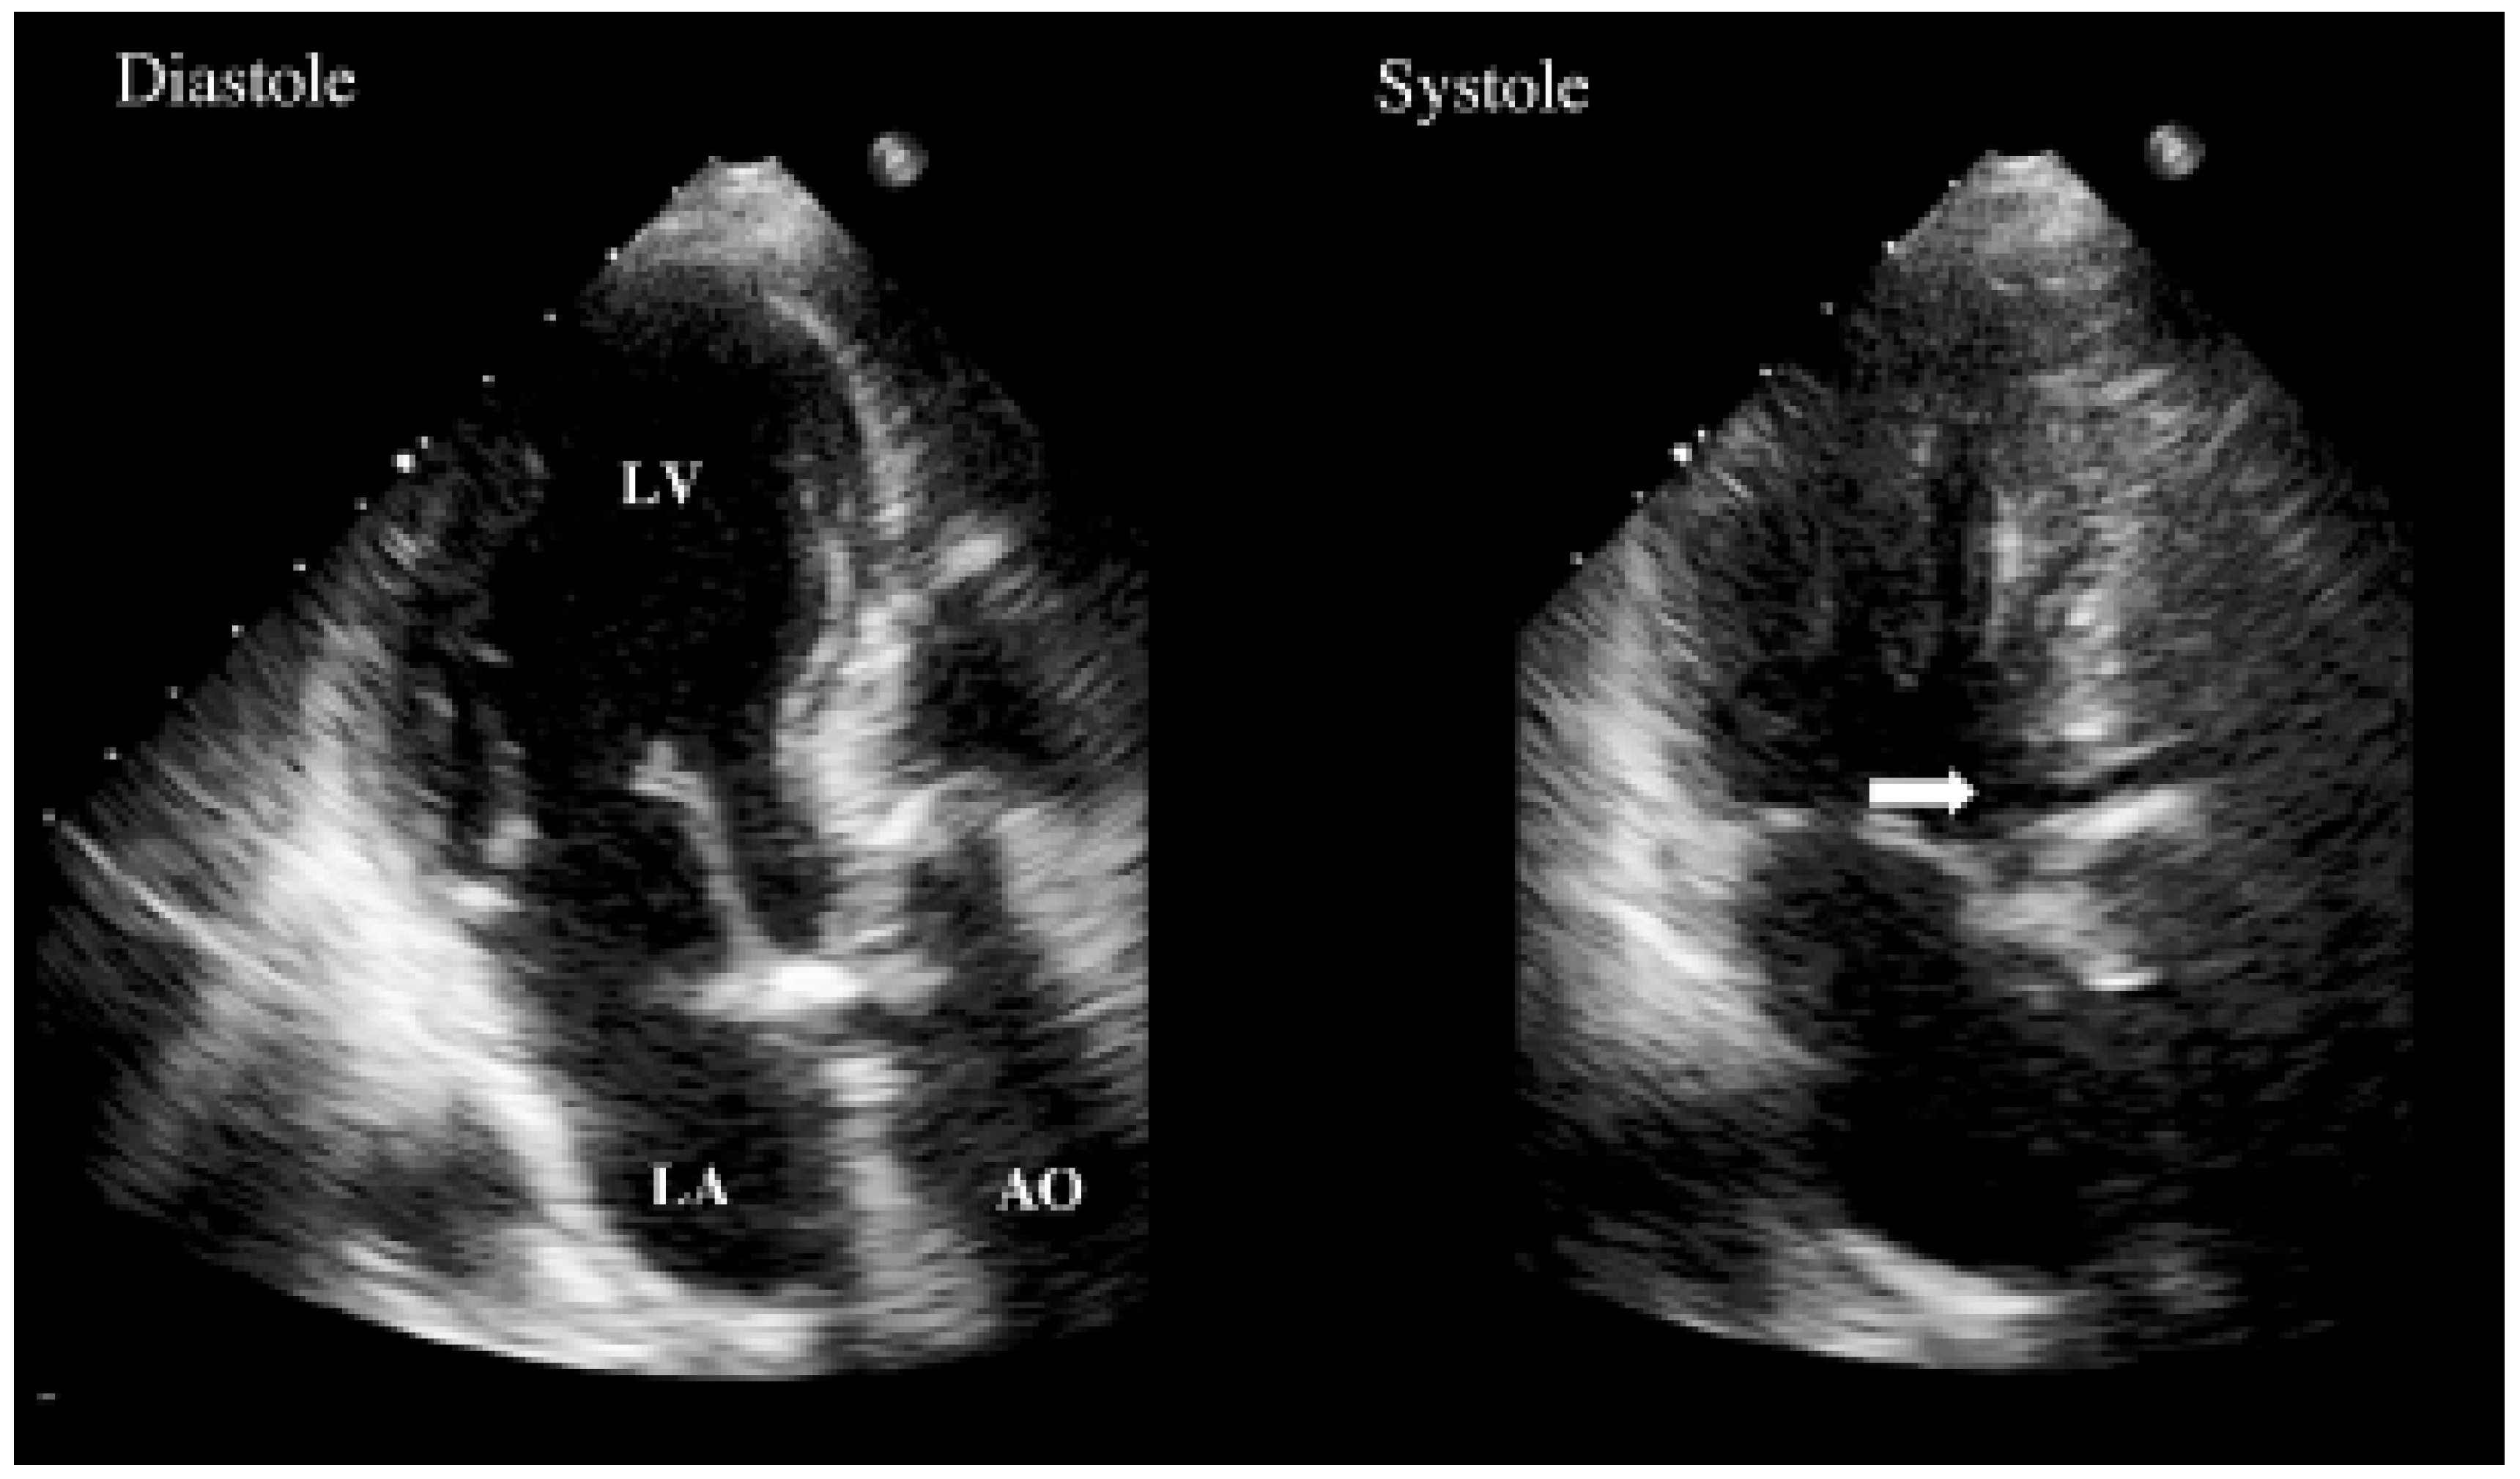

Transthoracic echocardiography was performed with only apical views available (Figure 1). It demonstrated abnormal motion of the prosthesis annulus but only a mild aortic insufficiency. Neither vegetations nor abscess were visualised. As the probability of prosthetic endocarditis was high, a transoesophageal echocardiography (Figure 2 and Figure 3) was organised immediately afterwards. It demonstrated a partially dehiscent prosthesis due to a subjacent hemicircumferential paraprosthetic abscess. This abscess has spontaneously drained, leaving a large cavity. Large vegetations were also observed on the leaflets of the bioprosthetic valve.

Figure 3. (A) TEE short axis view. Paravalvular abscess cavities from 1 o’clock to 7 o’clock position (*), extending from the anterior part of the annulus along the main pulmonary artery. The cavities are irrigated. (B) Large amount of vegetations fixed on bioprosthetic leaflets.